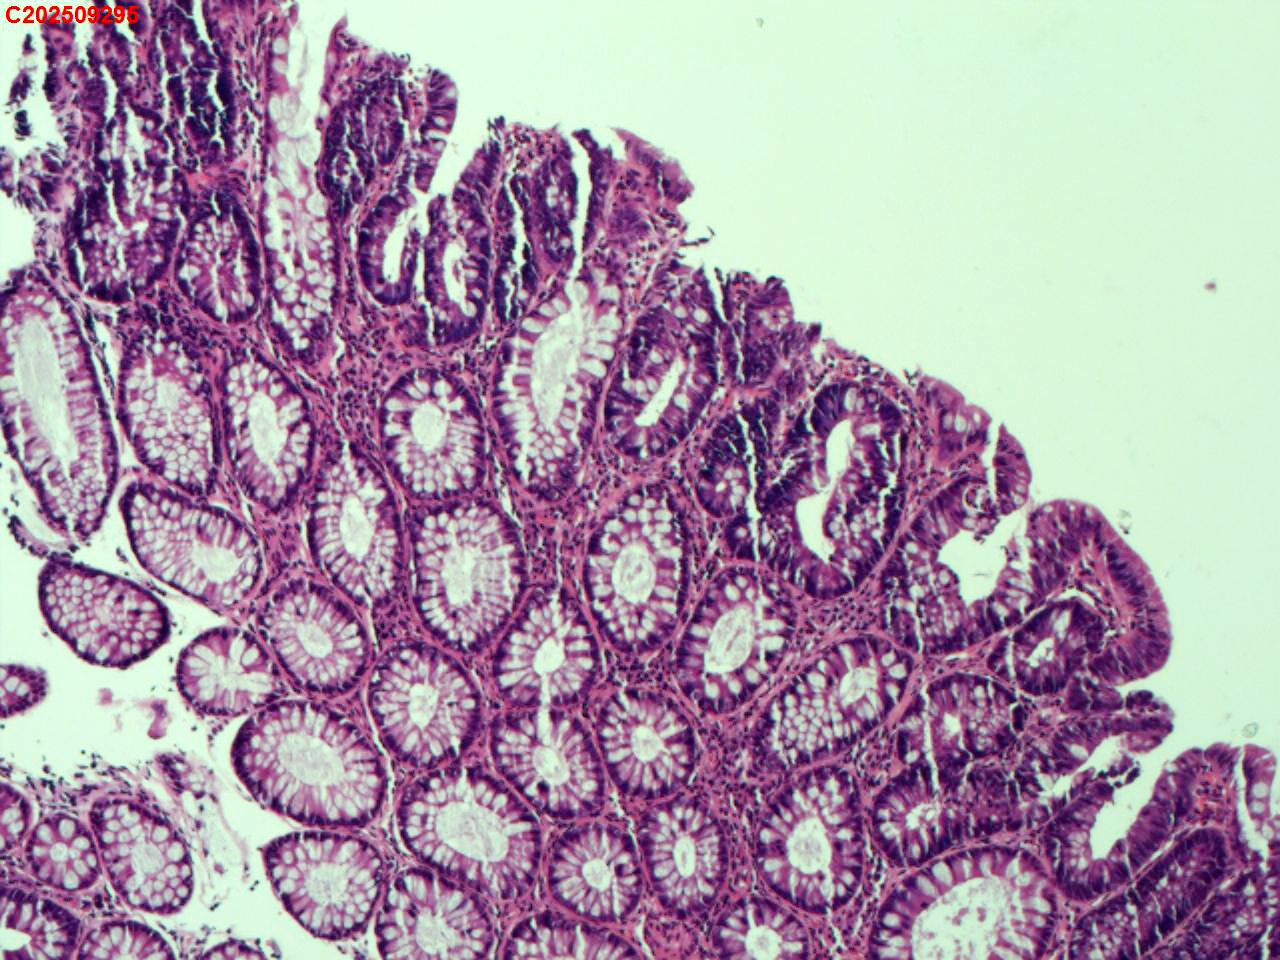

降结肠粘膜

性别

男

年龄

48岁

临床诊断

结肠息肉

一般病史

体检

标本名称

大体所见

降结肠:可见一枚直径约3mm息肉。

低级别管状腺瘤

管状腺瘤。